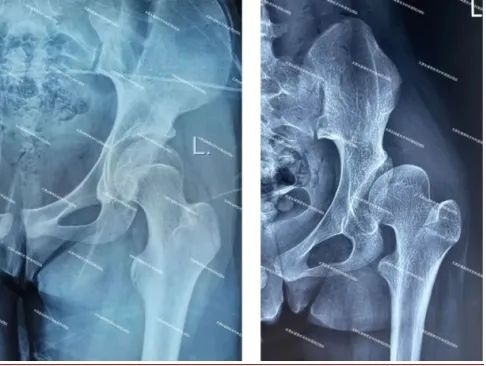

图7:术后影像(髋臼对股骨头的包容良好)该手术的实施标志着我院保髋医疗技术在骨科领域的重大突破、填补了区域技术空白,为更多髋关节发育不良患者提供了新的治疗选择。

(正常髋关节X线(左图)显示髋臼对股骨头的包容良好;发育不良髋关节X线(右图)显示髋臼对股骨头的包容不足。)我国人口众多,普查筛查水平相对不足,导致患者数量巨大,而疾病发现晚和处理晚。通常青少年或成人的DDH初期无明显临床症状,但随着病情进展,患者会出现髋关节周围疼痛。